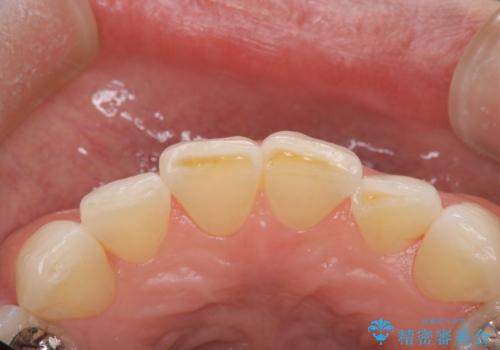

前歯の形気になる セラミッククラウン(SP)

- 矯正終了した患者様で、前歯の形が気になるということで

セラミッククラウンにて治療された方の症例です。

患者様と何度か修正を加えながら歯の形、色に満足していただけました。